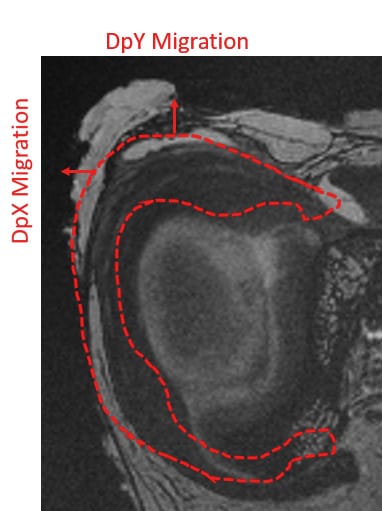

The displacement fields were analyzed in all three dimensions, but the observation of the displacements in x and y made it possible to analyze the anteroposterior and/or lateromedial migration of the meniscus after axial compression, with the knee positioned in full extension (Figure 4).

In the lateromedial direction (DpX), the mean displacements measured at 1500 N load were -2.809 (±0.778) on the first native knee versus -4.480 (±9.570) on the same knee with ramp lesion injury. For the second knee, the mean displacements measured in X with this same load were 2.108 (±0.380) before and 4.705 (±0.884) after ramp lesion injury. With a grade 4 medial meniscal ramp lesion, the meniscus increases its extrusion in the frontal plane (Figure 5 & 7).

In the anteroposterior direction (DpY), the mean displacements measured at 1500 N load were 0.476 (±0.552) on the first native knee versus 3.285 (±0.819) on the same knee with ramp lesion injury. For the second knee, the mean displacements measured in Y with this same load were 2.112 (±0.378) before and 7.311 (±1.312) after ramp lesion injury. With a grade 4 ramp lesion, the posterior segment of the medial meniscus increases its posterior extrusion in the sagittal plane (Figure 6 & 8).